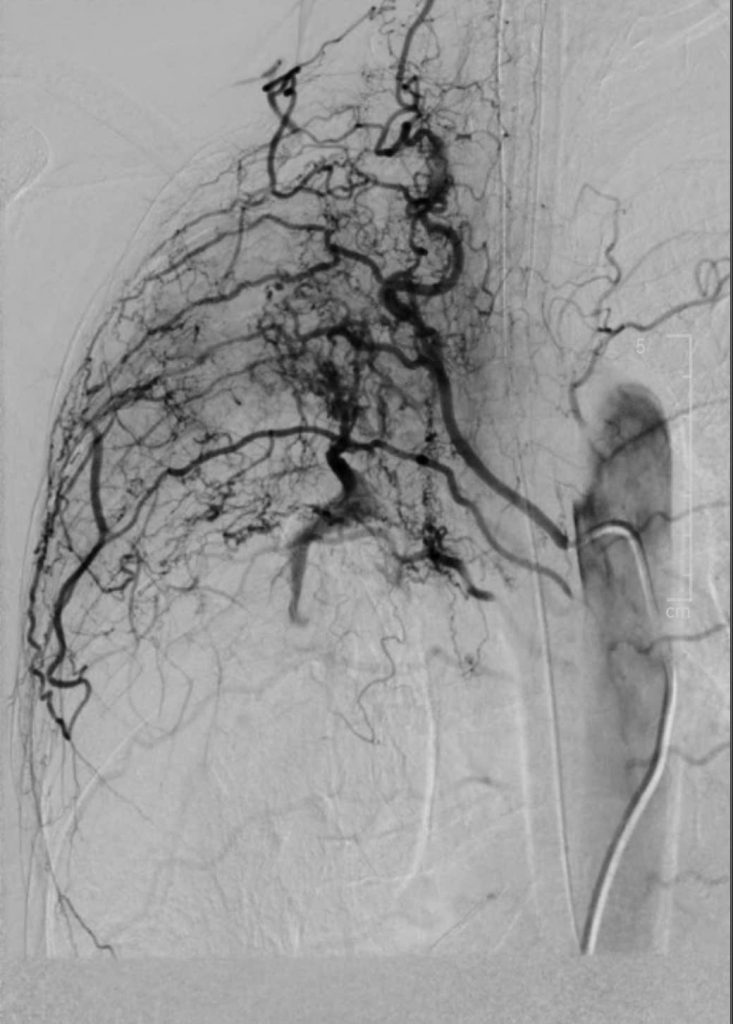

Quá trình can thiệp tắc động mạch phế quản

BS.CKI. Trịnh Đình Hiếu – Đơn vị Can Thiệp Mạch Bệnh viện Đa khoa Xuyên Á, người trực tiếp thực hiện thủ thuật cho biết: “Trong quá trình can thiệp, các bác sĩ Đơn vị Can Thiệp Mạch đã phối hợp cùng các bác sĩ khoa Gây Mê Hồi Sức và khoa Hồi Sức Tích Cực để ổn định tình trạng huyết động của bệnh nhân. Qua đường ống nhỏ luồn từ động mạch đùi, các bác sĩ Đơn vị Can Thiệp Mạch đã đưa dụng cụ chuyên dụng đến tận nhánh động mạch phế quản bị tổn thương và tiến hành tắc mạch máu tổn thương bằng chất tắc mạch, kiểm soát được nguồn máu chảy và giảm nguy cơ ho ra máu tái phát về sau.”

Hình ảnh trước can thiệp